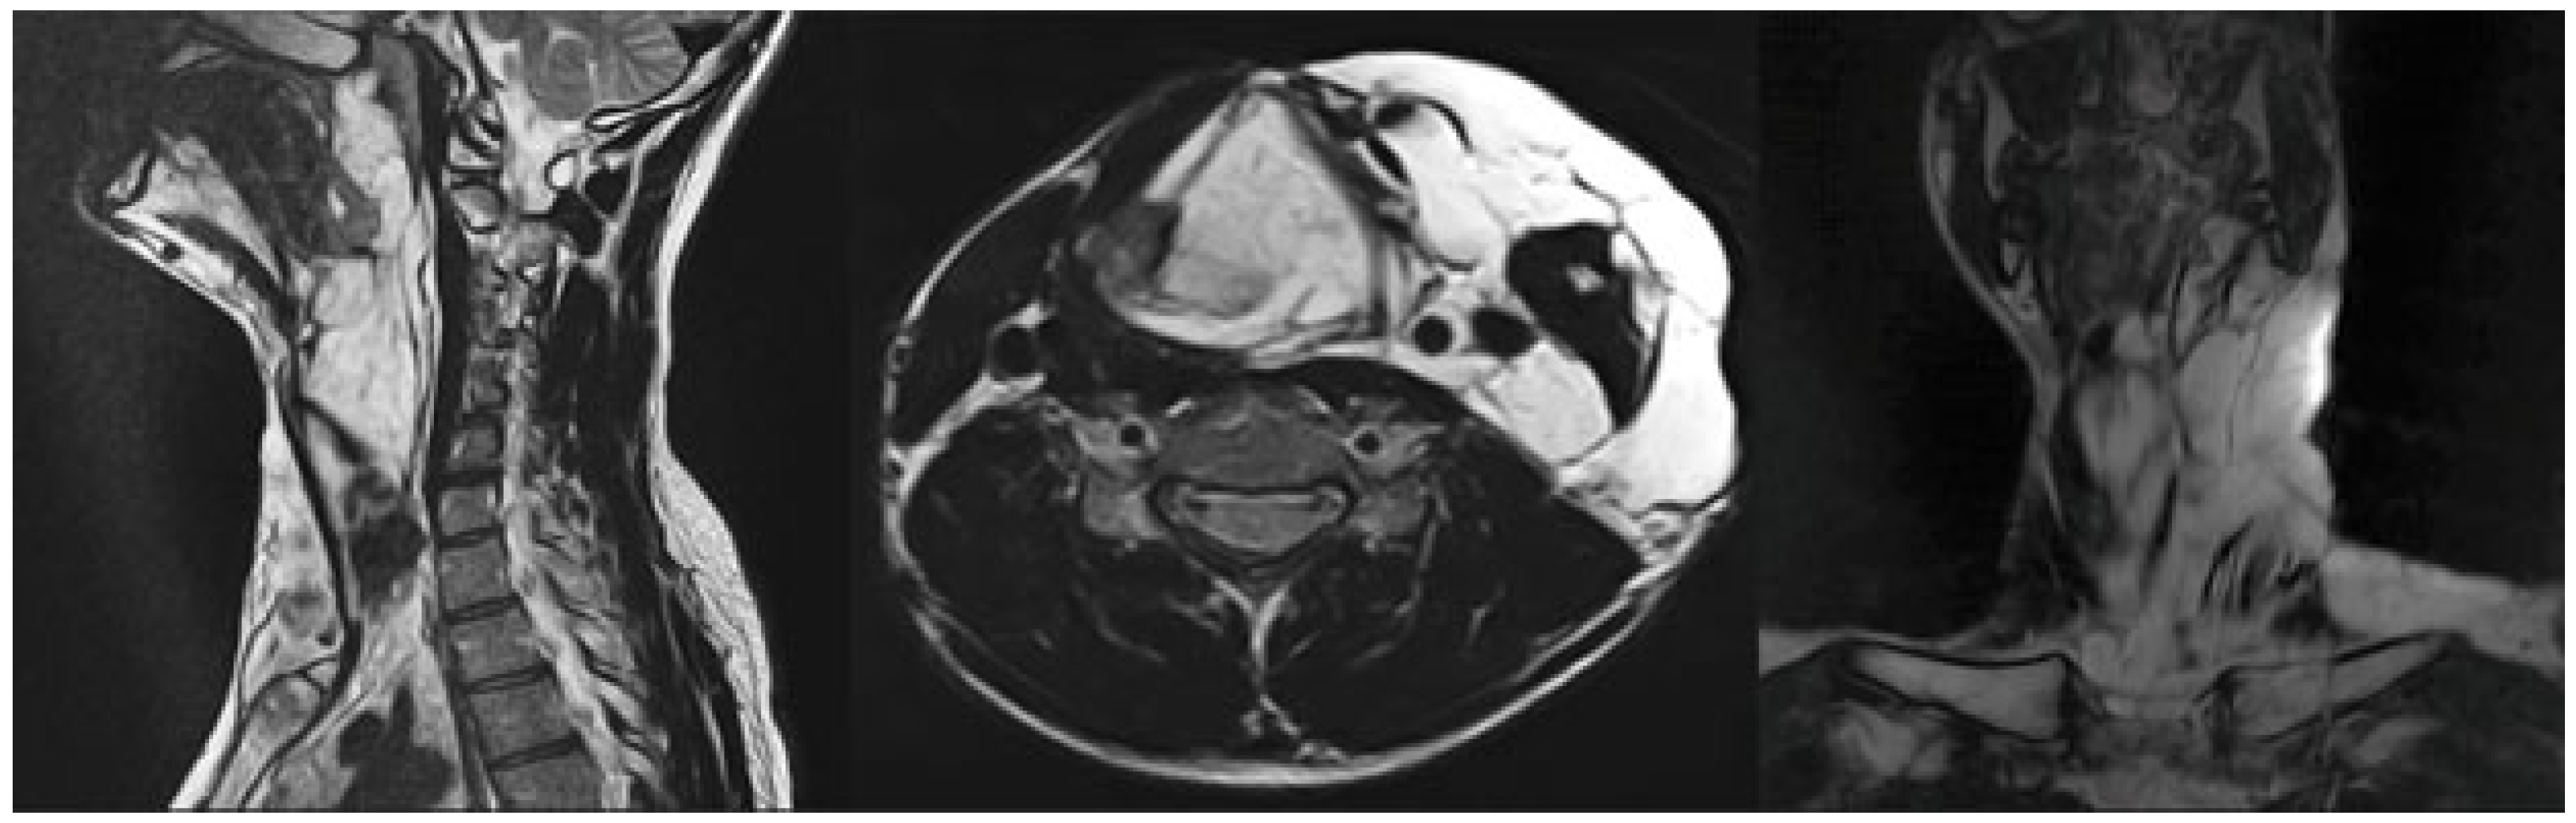

3.1. Magnetic Resonance Imaging (MRI) Findings